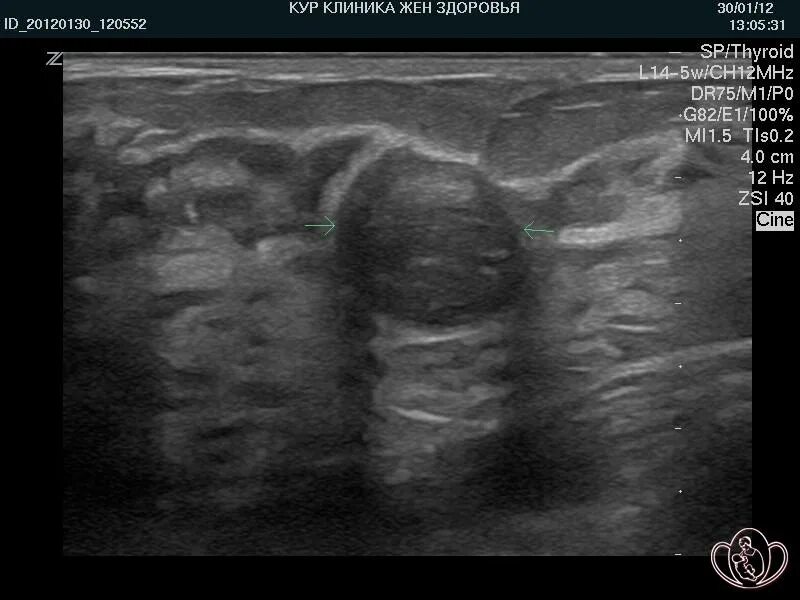

Как выглядит фиброаденома молочной железы